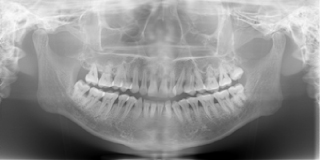

◆歯周病の診査

歯を支える骨の状態を立体的にとらえることで、より精密な歯周病の診断を可能にします。3D画像では歯を支える骨の状態までリアルに再現できますから、初期の歯周病も発見が可能となります。

◆親知らずの診断

三次元画像の活用で、歯の神経の位置や歯の根の状態や形状まで正確に把握することができ、より安全で確実な抜歯が可能となります。

◆歯の神経の治療

歯の根の位置や側枝(枝分かれしている根)の状態、歯の根の先端の病巣の状態などが、三次元画像で、正確に把握できます。